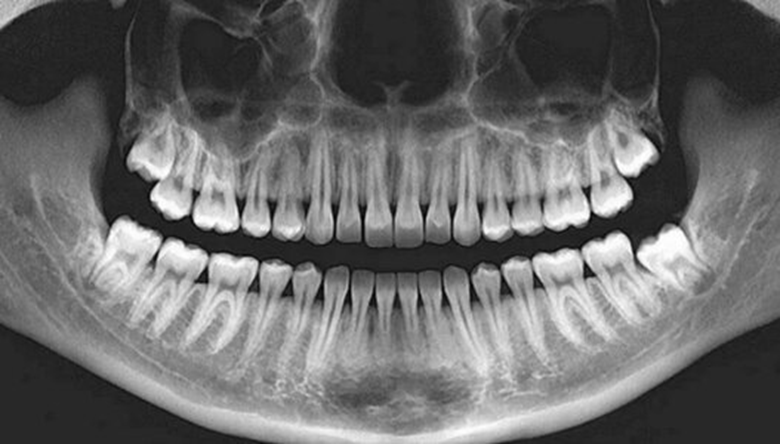

Процедура рентгенографии зубов подразумевает использование рентгеновских лучей для создания изображения внутренней структуры зубов и костей челюсти. В стоматологической практике применяются различные виды рентгена, например:

- панорамное изображение всей челюсти;

Каждый из этих методов выбирается в зависимости от конкретной ситуации и задач, стоящих перед врачом. Прицельный рентген позволяет детально изучить отдельные зубы или небольшие участки, панорамный охватывает обе челюсти и дает общее представление о состоянии зубного ряда, а компьютерная томография позволяет получить объёмное изображение для сложных случаев, таких как установка имплантов или выявление скрытых патологий.